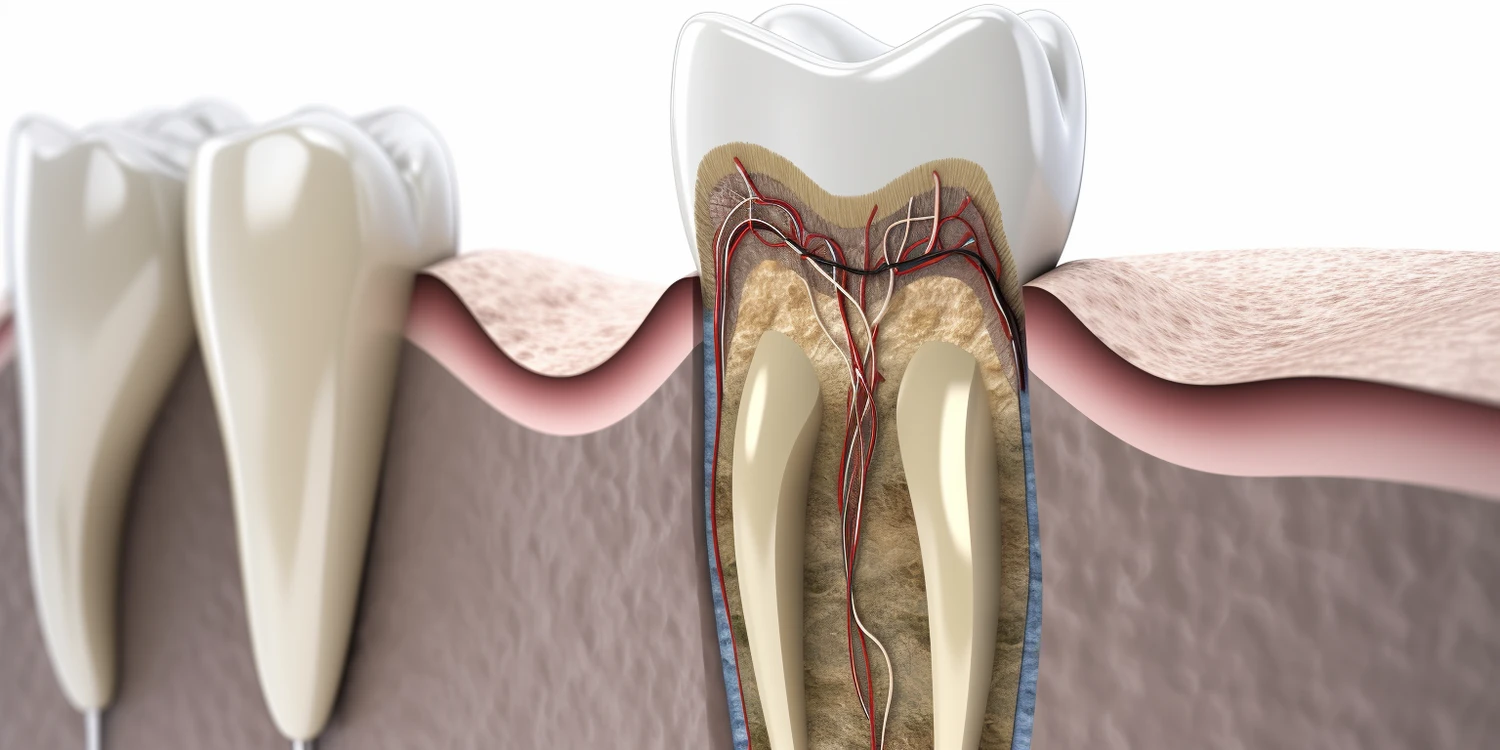

Leczenie kanałowe składa się z kilku kluczowych etapów, które mają na celu skuteczne usunięcie zakażonej tkanki oraz zabezpieczenie zęba przed dalszymi problemami. Pierwszym krokiem jest dokładna diagnostyka, która obejmuje zdjęcia rentgenowskie oraz ocenę stanu zęba. Ten etap może zająć od 30 do 60 minut. Następnie stomatolog przystępuje do znieczulenia pacjenta i otwarcia komory zęba, co również zajmuje około 30 minut. Kolejnym krokiem jest usunięcie miazgi oraz oczyszczenie i opracowanie kanałów korzeniowych. To najważniejsza część zabiegu i może trwać od jednej do kilku godzin w zależności od liczby kanałów oraz stopnia skomplikowania. Po zakończeniu oczyszczania lekarz wypełnia kanały materiałem uszczelniającym i zamyka komorę zęba.

W ostatnich latach rozwój technologii w dziedzinie stomatologii, a szczególnie endodoncji, znacząco wpłynął na efektywność i komfort leczenia kanałowego. Jednym z najważniejszych osiągnięć jest zastosowanie mikroskopów operacyjnych, które pozwalają stomatologom na dokładne zobrazowanie wnętrza zęba oraz precyzyjne opracowanie kanałów korzeniowych. Dzięki temu możliwe jest skuteczniejsze usunięcie zakażonej miazgi oraz minimalizacja ryzyka uszkodzenia zdrowych tkanek. Inną nowoczesną technologią są systemy rotacyjne do opracowywania kanałów, które znacznie przyspieszają proces leczenia i poprawiają jego jakość. Dodatkowo, zastosowanie materiałów biokompatybilnych do wypełniania kanałów korzeniowych zwiększa szanse na długotrwałe powodzenie zabiegu. Warto również wspomnieć o cyfrowym obrazowaniu, które umożliwia szybsze i dokładniejsze diagnozowanie problemów stomatologicznych.